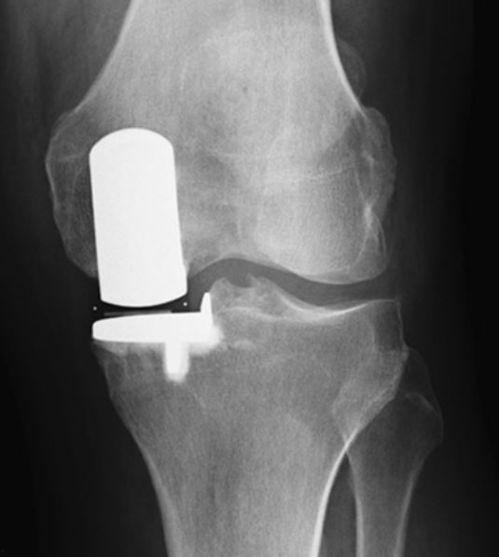

视频中的画面让人惊叹,医生的手法非常熟练。他们小心翼翼地移除受损的关节,然后放入人工关节。这个过程需要精确的测量和操作,以确保人工关节能够完美地替代受损的关节。